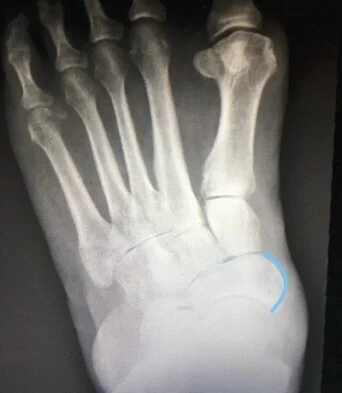

The Podiatrist would order an xray also Ultrasound and/or MRI.  Evaluation of the foot and ankle is performed by the Podiatrist testing muscle strength both on the exam table standing and walking.  Always compare the affected to non-affected foot.  The Podiatrist will have the patient stand on the painful foot with the other foot in the air and ask the patient to heel raise.  In performing this test this can be painful or the patient can be unable to do the heel raise and or cannot turn in (invert) the heel.  Depending on the inability to invert the heel and strength of the tendon different treatment options would be chosen.